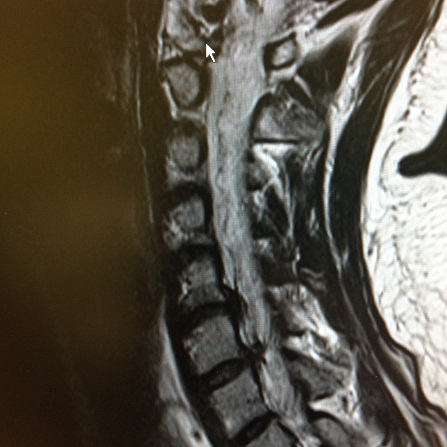

Unsere Einrichtung ist spezialisiert auf minimalinvasive Wirbelsäulenbehandlung: Wir nutzen sämtliche Formen der Wirbelsäuleninfiltrationstherapie und -diagnostik ( z.B. Facetteninfiltration, PRT) und Denervierungstherapie in moderner Technik. Auf diese Weise können , eingebettet in ein funktionelles Programm, die meisten Probleme am Rücken behandelt werden. Manchmal ist aber eine Operation nicht zu vermeiden. Gemeinsam ist allen Prozeduren die individueller Therapieplanung und ein besonders schonendes, wenig belastendes Vorgehen.

Dr Godon hat sich seit Jahren auf die konservative und operative Behandlung von Wirbelsäulenerkrankungen spezialisiert. Seit 1992 führt er operative Wirbelsäuleneingriffe durch. Bereits vor Jahren erfolgte die Spezialisierung zu minimalinvasiven Eingriffen: 1997 die CT-gestützte periradikuläre Therapie Grönemeyer, 2002 die endoskopische Operation (Thessys) von Bandscheibenvorfällen, einem Verfahren, das heute die schonende ambulante oder kurzstationäre Behandlung ermöglicht, die Nucleoplastie Behandlung erkrankter Bandscheiben und Hyaluronsäure- und Kryotherapie bei Arthrose der kleinen Wirbelgelenke